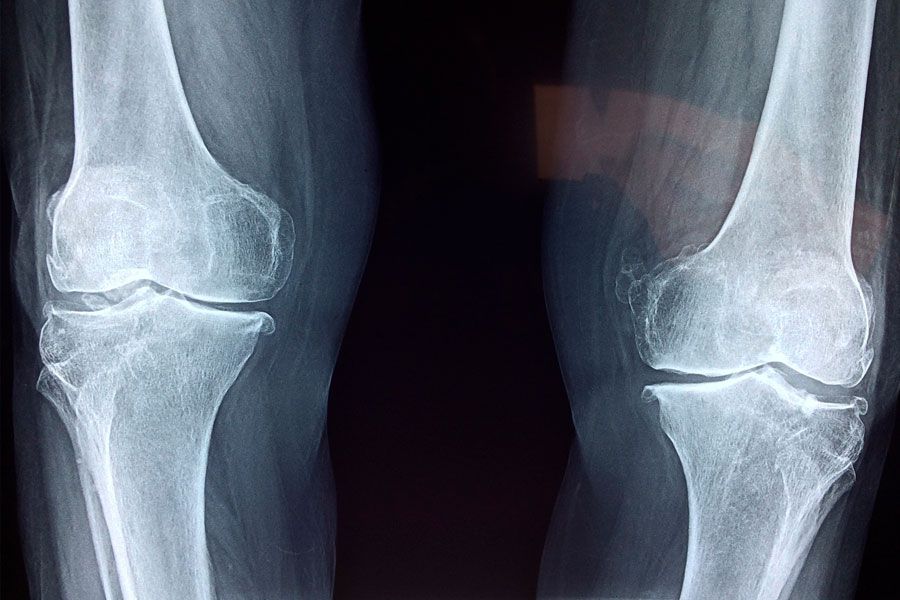

Consultado sobre la complejidad funcional de la rodilla y el auge de la cirugía, Druetto sostuvo: “La triada típica de la lesión de rodilla es la ruptura del ligamento cruzado, el menisco interno y el ligamento colateral medial. Es muy raro que el deportista de alto rendimiento tenga una lesión solo de cruzado. Lo más importante, porque nos da inestabilidad a futuro, es la ruptura del ligamento cruzado”.